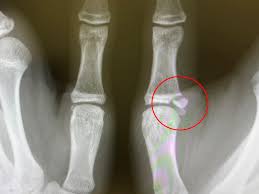

(4) 건초염 및 방아쇠수지

- 손가락을 구부릴 때 “딸깍” 소리가 나고, 펴기 어려우며 마디가 아픈 경우 방아쇠수지를 의심할 수 있습니다.

- 손가락 굽힘을 담당하는 힘줄 부위에 염증이 생기며, 주로 엄지, 중지, 약지에 발생합니다.

(3) 주사치료

- 관절 내 스테로이드 주사로 염증 완화

- 방아쇠수지에는 국소마취제 + 스테로이드 주사가 사용됩니다.

(4) 수술